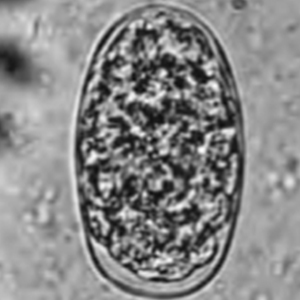

Molineus eggs have a typical non-embryonated strongyle egg morphology: they are oval, with a thick outer membrane, a morula and non-parallel lateral sides. They also have characteristics of Trichonstrondyloidea eggs with one of their side being thinner, and contain a dense morula of 16 to 32 blastomeres. They measure 40 to 52 µm long and 20 to 29 µm large. It is impossible to distinguish different species of Molineus by ovodiagnosis (Cogswell, 2007).

Differential diagnosis includes other species of Trichostrongyloidea nematodes, namely Nochtia nochti. Moreover, it should not be confused with other non-embryonated strongyle eggs.